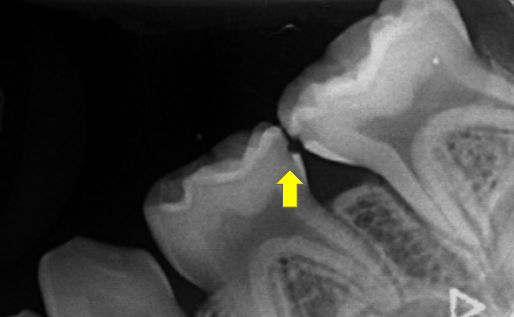

歯の間の虫歯のレントゲン(乳歯)

お子様の歯は小さく、歯と歯の間もぴったりくっついているため、虫歯を見つけるのが難しい場合があります。

マイクロスコープを使っても、見落としてしまうことがあるんです。

そのため、レントゲン検査でお口の中をしっかり確認することが大切です。

他院で虫歯がないと言われたにもかかわらず、突然歯の間に穴があいて来院されるお子様が多くいらっしゃいます。このような場合、レントゲン撮影を行うと、他にも3箇所の歯の間に虫歯が見つかることがあります。

お子様の歯のレントゲン撮影は極めて困難を伴います。口腔内が狭小である上、デジタルフィルムの挿入を要するため、短時間での撮影が不可欠です。これは小児歯科において、スタッフが習熟していなければ実現不可能です。